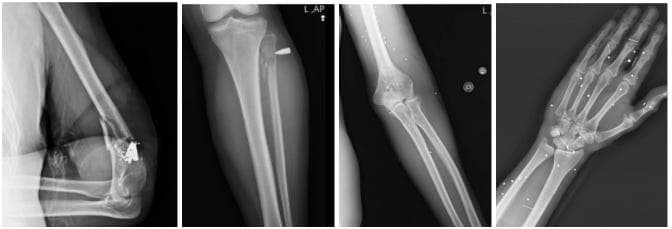

4. Arms and legs

Many scans showed comminuted fractures—bones shattered into multiple fragments consistent with high-energy ballistic trauma.

Pellet scatter around the knees and thighs appeared frequently. Even when bones were intact, the risk of nerve and vascular damage remained significant. One case involved a lower-leg amputation, though its exact cause could not be definitively attributed to gunfire.

Comminuted fracture around the elbow joint with metal fragments, diaphyseal fractures of the forearm bones consistent with projectile penetration, and multiple pellet dispersions in the hand and wrist.